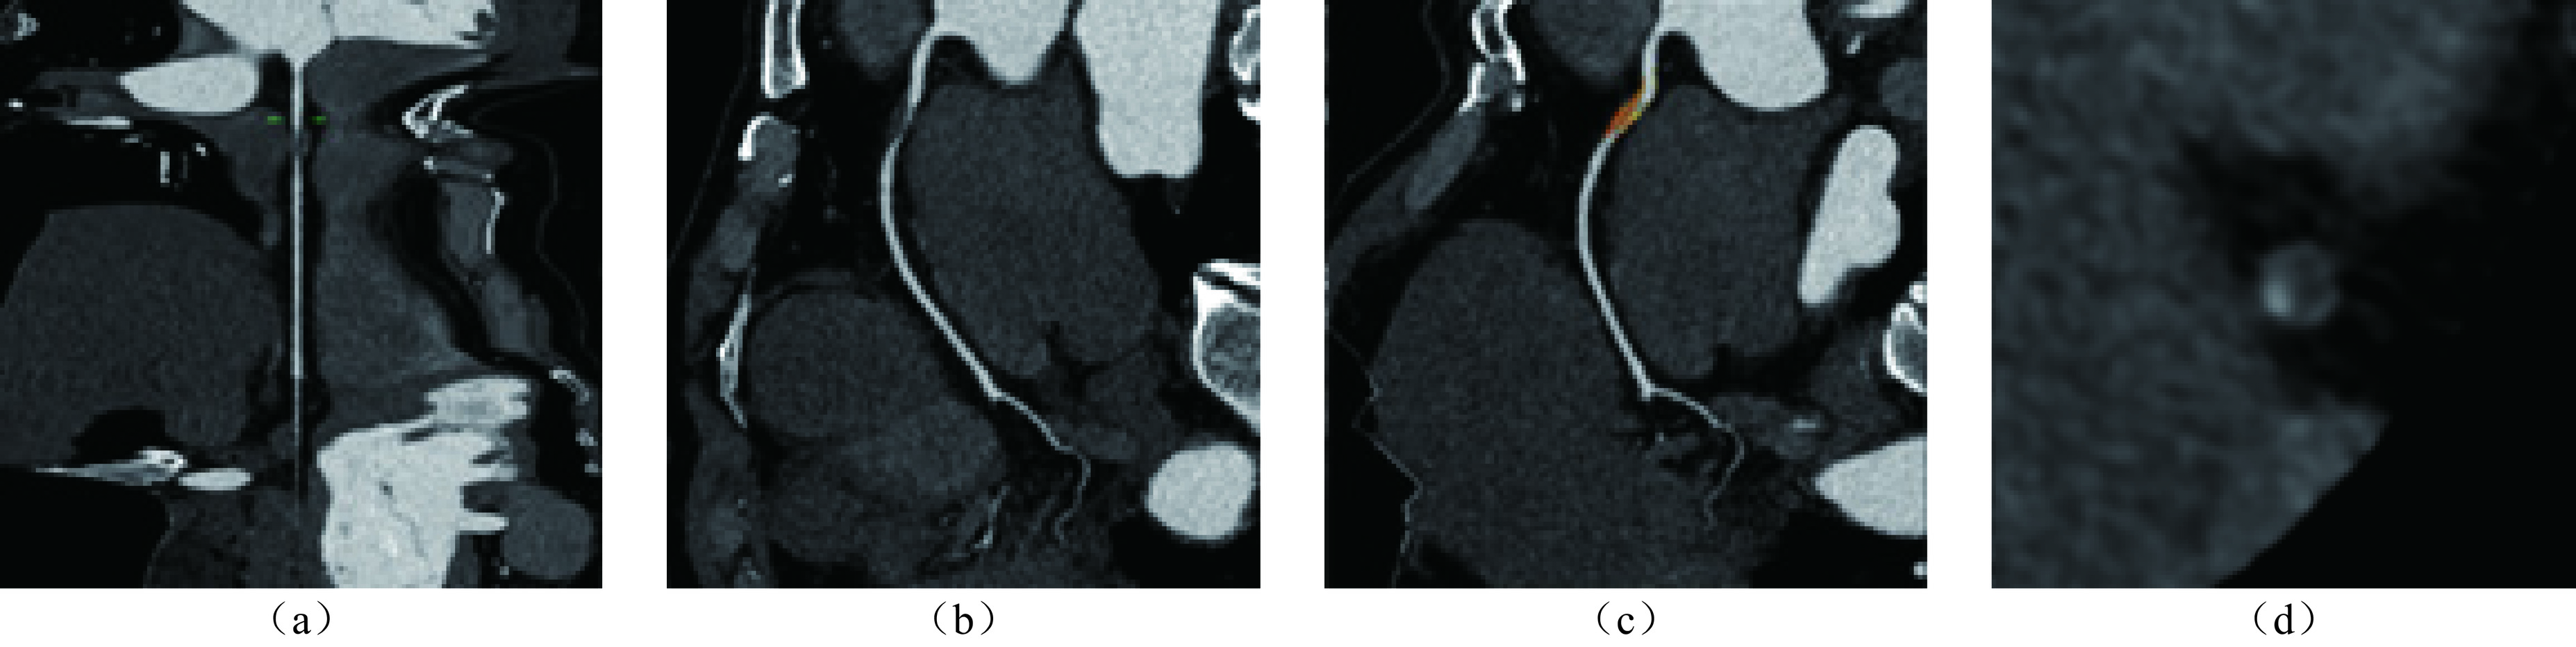

目的:比较缺血组与非缺血组的CCTA斑块特征差异,探求对诊断心肌缺血有价值的斑块特征定性及定量指标,在临床工作中应用,尽早发现可能存在心肌缺血的受检者。方法:连续纳入2022年1月至2024年12月就诊于我院心内科并接受有创冠状动脉造影测量FFR和CCTA扫描的冠心病患者进行回顾性分析。以患者水平分组分析一般资料。以血管水平分组分析CCTA斑块特征信息。斑块分析由两名具有5年以上CCTA诊断经验的放射科医师在未知分组的情况下使用半自动斑块分析软件进行。结果:研究共纳入163例患者,缺血患者组与非缺血患者组的一般资料无统计学显著差异。本研究共纳入253支血管,缺血血管组纳入114支血管,非缺血血管组纳入139支血管。斑块特征定性指标中,缺血血管组的餐巾环征、点状钙化比例高于非缺血血管组,两组的正性重构、低密度斑块指标无统计学显著差异。斑块定量指标中,两组的PL、PB、MLA、MDS、MAS、RI具有统计学显著差异,PV、EI无统计学显著差异。PL、PB、MLA、MDS、MAS、RI诊断斑块所属血管供血区域的心肌缺血的AUC分别为0.672、0.712、0.843、0.830、0.821、0.655,联合检测的AUC为0.844,高于单一指标诊断。结论:CCTA斑块特征分析在预测心肌缺血中具有很大潜力,多种斑块特征定量指标联合诊断对预测心肌缺血具有更高的效能。

Abstract:Objective: To compare the differences in coronary computed tomography angiography (CCTA) plaque characteristics between ischemic and non-ischemic groups and to explore qualitative and quantitative plaque features that are valuable for diagnosing myocardial ischemia. This study aimed to apply these indicators in clinical practice to identify patients with potential myocardial ischemia as early as possible. Methods: A retrospective analysis was conducted on patients with coronary heart disease who underwent invasive coronary angiography for fractional flow reserve (FFR) measurement and CCTA scanning in the cardiology department of our hospital between January 2022 and December 2024. General information was analyzed at the patient level, whereas CCTA plaque characteristics were analyzed at the vessel level. Plaque analysis was performed by two radiologists with more than five years of experience in CCTA diagnosis using semi-automatic plaque analysis software blinded to the patient groups. Results: A total of 163 patients were included in the study, with no statistically significant differences in general information between the ischemic and non-ischemic groups. A total of 253 vessels were included, with 114 vessels in the ischemic and 139 in the nonischemic vessel groups. Among the qualitative plaque characteristics, the napkin-ring sign and punctate calcification were more prevalent in the ischemic than in the nonischemic vessel group. No statistically significant differences were observed in positive remodeling and low-density plaque indicators between the two groups. Among the quantitative plaque characteristics, statistically significant differences in plaque length (PL), plaque burden (PB), minimum lumen area (MLA), minimum diameter stenosis (MDS), maximum area stenosis (MAS), and remodeling index (RI) were observed between the two groups. There were no statistically significant differences in plaque volume (PV) or edge irregularity (EI). The areas under the curve (AUCs) for diagnosing myocardial ischemia in the vascular supply areas of the plaques using PL, PB, MLA, MDS, MAS, and RI were 0.672, 0.712, 0.843, 0.830, 0.821, and 0.655, respectively. The AUC for the combined detection was 0.844, which was higher than that for any single indicator. Conclusion: CCTA plaque characteristic analysis has great potential for predicting myocardial ischemia, and the combined use of multiple quantitative plaque indicators provides higher diagnostic efficacy.